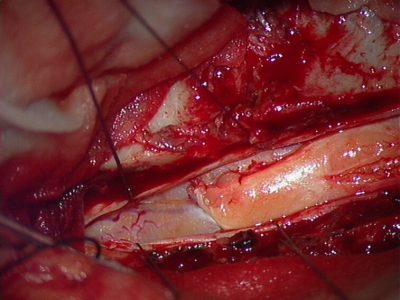

Χειρουργική Αντιμετώπιση: Οι ενδείξεις και ο τρόπος χειρουργικής αντιμετώπισης εξαρτώνται απολύτως από τον τύπο του όγκου. Πρωτοπαθείς (μη-μεταστατικοί) όγκοι των σπονδύλων χρειάζονται ριζική αφαίρεση με σπονδυλεκτομές. Σε περίπτωση μεταστάσεων συνήθως αρκεί η αποσυμπίεση των νευρικών δομών και η συμπληρωματική ακτινοβολία. Το αν υπάρχει ένδειξη για χειρουργείο σε ασθενή με μεταστατική νόσο σπονδυλικής στήλης είναι κάτι που πρέπει να συζητηθεί και να συναποφασιστεί με τους ογκολόγους. Για ενδοσκληρίδους όγκους όπως πχ. μηνιγγιώματα ή νευρινώματα, καθώς επίσης για ενδομυελικούς όγκους (πχ. αστροκυττώματα ή επενδυμώματα) η θεραπεία είναι η ολική χειρουργική αφαίρεση. Συνήθως χρησιμοποιούνται ελάχιστα επεμβατικές μέθοδοι ενώ αποφεύγεται η καταστροφή των υγιών ιστών και δομών της σπονδυλικής στήλης (Εικόνα 3). Μερικοί όγκοι, όπως πχ. το λίπωμα νωτιαίου μυελού, αφαιρούνται ιδιαίτερα αποτελεσματικά με τη χρήση λέιζερ (laser) (Εικόνα 4).

Εικόνα 3: Αριστερά: Αποκάλυψη της μήνιγγας, λίγο πρίν τη διάνοιξή της για ενδομυελικό όγκο. Δεξιά: Μετά την ολοκλήρωση της αφαίρεσης της βλάβης, επανατοποθέτηση των ακανθωδών αποφύσεων και αποκατάσταση της ανατομίας της σπονδυλικής στήλης (Πεταλοπλαστική).(προσωπικό αρχείο νευροχειρουργού Π. Σταυρινού).